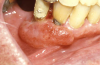

Extrinsic antigenic sources such as drugs have been identified as agents responsible for oral lichen planus (OLP)-like lesions. Drugs such as NSAIDs and ACE inhibitors can act as haptens and alter the antigenicity of epithelial self-antigens. OLP that can be traced to an extrinsic cause is more properly termed a lichenoid reaction.8,13-16 Oral lichenoid lesions most often affect the buccal mucosa (Figure 12 and Figure 13), gingivae, the lateral border of the tongue and may be “reticular,” erythematous, or atrophic.

Figure 12. Lichenoid stomatitis in a patient with rheumatoid arthritis taking ibuprofen.

Figure 12

Figure 13. Lichenoid stomatitis in a patient with rheumatoid arthritis taking ibuprofen.

Figure 13